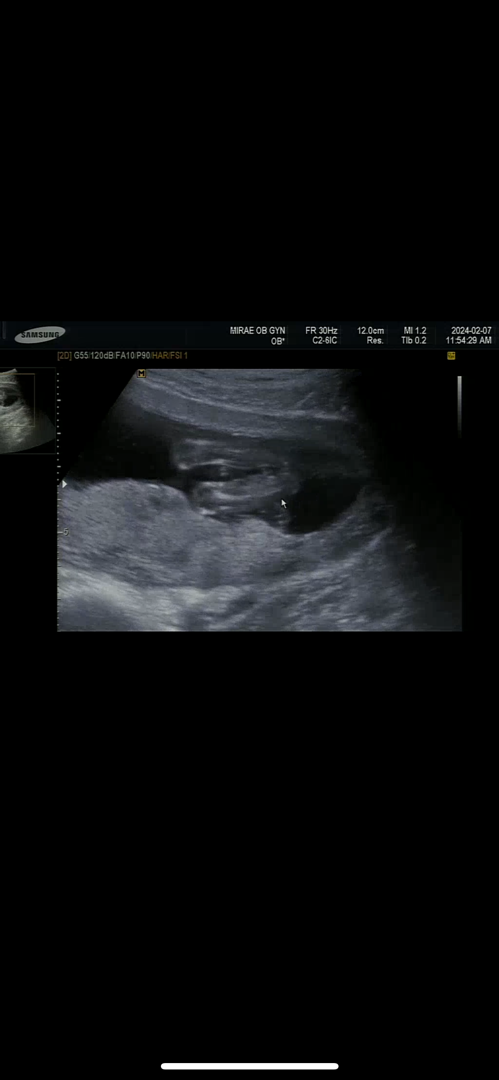

성별 봐주세요ㅎㅎ

딸일까요?아들일까요?ㅎㅎ

16주입니다!

다리늘 좀 오므리고 있어서 잘 안보이지만 무언가 나와있는거 같기도 하구요🙂😁